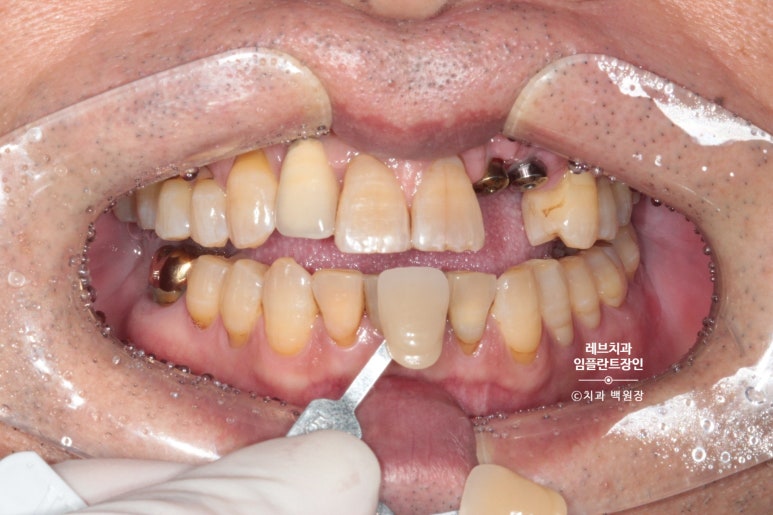

역시나 치아 색을 정하기 위해 shade guide를 이용하여 치아색 측정을 열심히 해봅니다.

어른들의 치아를 자세히 보시면, 생각보다 색구현이 어렵게 생겼음을 확인하실 수 있을거에요 ^^;;;

그리하여 유사하게 만들어본 앞니입니다.

왼쪽 위 작은 앞니와 송곳니를 합쳐서 2개짜리 보철물을 만들었어요!